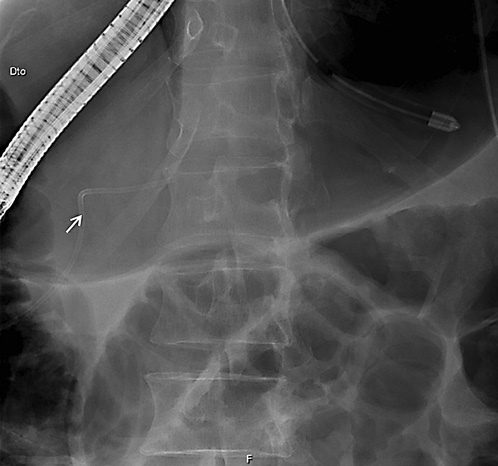

On ERCP, the Wirsungogram identified a point of ductal leak-age in the body of the pancreas, with contrast spreading to the middle of the column (most likely to the pseudocyst lumen) (Fig. 3). Pancreatic sphincterotomy and placement of a double-flanged straight 5-Fr plastic stent with 9 cm (the longest one avail-able in the unit) in the duct of Wirsung, up to the ductal disruption site (Fig. 4), were performed.

Fig. 3 Wirsungogram performed on the first endoscopic retrograde cholangiopancreatography, revealing a ductal leakage in the body of pancreas (white arrow).